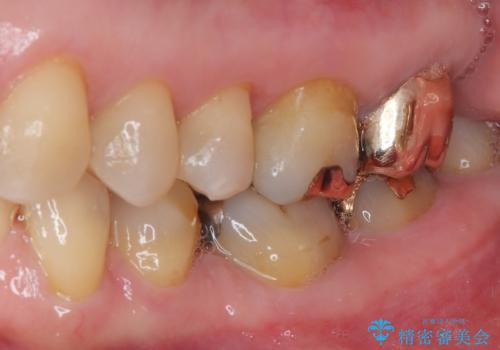

拡大鏡視野下で、保険のプラスチック、虫歯の除去を行い、セラミックインレーに適した形に整えました。

歯と歯茎の間に圧排糸と言われる糸を入れてシリコーン印象材にて精密な型どりをしました。

歯と歯の間の虫歯をコンポジットレジンや保険のメタルインレーで治すと段差ができたりして清掃性が悪くなるので、セラミックインレー修復やゴールドインレー修復などの適合の良い詰め物で治療することをオススメします。